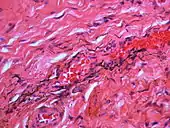

If necessary, the diagnosis can be confirmed histologically by excisional biopsy, which excludes nevi and melanomas.[3]: 138 If a biopsy is taken, the histopathologic appearance is:[1]

- Pigmented fragments of metal within connective tissue

- Staining of reticulin fibers with silver salts

- A scattered arrangement of large, dark, solid fragments or a fine, black or dark brown granules

- Large particles may be surrounded by chronically inflamed fibrous tissue

- Smaller particles surrounded by more significant inflammation, which may be granulomatous or a mixture of lymphocytes and plasma cells